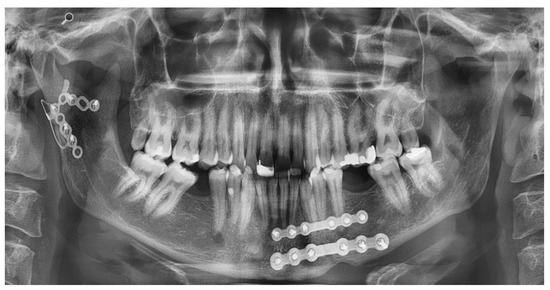

Application of the Plates